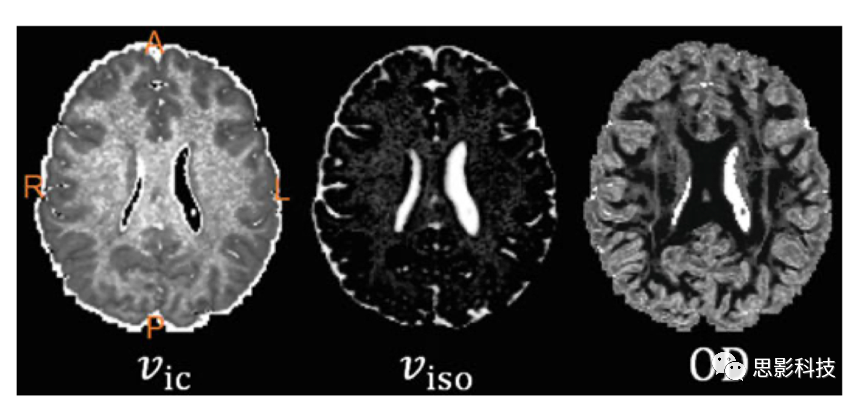

2)神經(jīng)突方向散度和密度成像(neurite orientation dispersion and density imaging,NODDI

NODDI方法主要對(duì)全腦神經(jīng)突方向散度和密度進(jìn)行成像??梢杂?jì)算vic、viso、OD等標(biāo)量指標(biāo)進(jìn)行進(jìn)一步基于體素的統(tǒng)計(jì)分析。

圖例 NODDI指標(biāo)